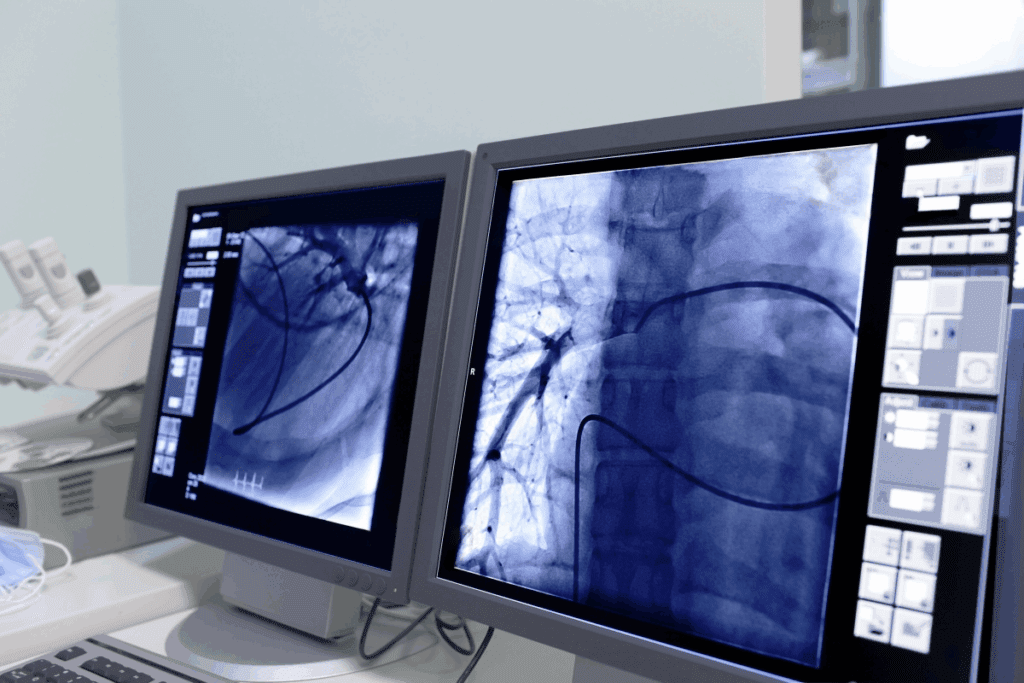

Fluoroscopy gives us real-time X-ray images. This lets us see instruments and devices moving during procedures. It’s very helpful for vascular interventions, helping us place stents and balloons accurately.

DSA is a fluoroscopic method for vascular imaging. It subtracts pre-contrast images from post-contrast ones. This gives clear views of blood vessels, without the interference of bone and soft tissue. It’s vital for vascular imaging and guiding interventions.

Angioplasty and stenting are key vascular interventions. They help widen narrowed or blocked arteries. Angioplasty uses a balloon to push plaque against the artery walls. Stenting places a metal mesh tube to keep the artery open.

These procedures are vital for treating coronary artery disease and peripheral artery disease. They have the advantage of shorter recovery times and can be done under local anesthesia. But, there are risks like bleeding, infection, and stent thrombosis.